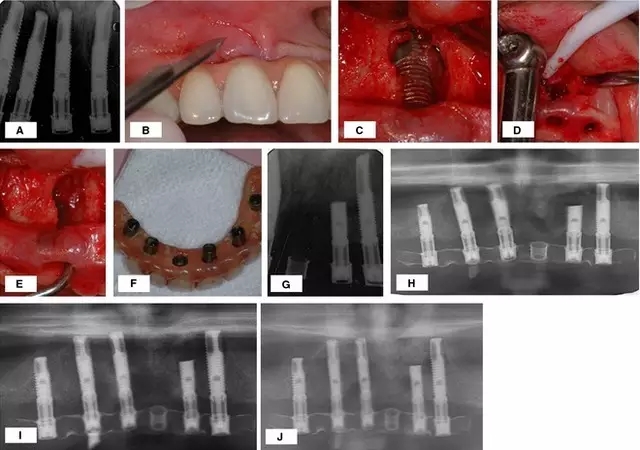

對于種植體周圍炎引起的骨缺損,有學者應用骨替代材料取得了很好的治療效果。Quirynen 等應用去蛋白的牛骨粉成功的治愈了種植體周圍炎引起的骨缺損,治療方法如圖 1。

圖 1 :(A)患牙拔除三月后根尖周 x 線片; (B) 種植體植入三月后出現(xiàn)根尖周病變 ;(C) 出現(xiàn)瘺管; (D) 翻起全厚黏骨膜瓣;(E –G) 骨缺損檢查,刮除病變組織,生理鹽水沖洗; (H) 植入骨替代材料,引導骨再生; (I)術(shù)后 4 個月口內(nèi) x 線片,基臺連接 ;(J,K)負載一年后